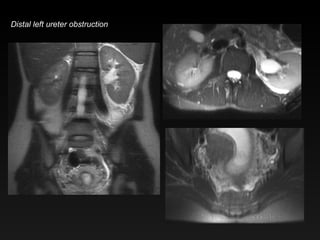

Distal left ureter obstruction

Distal left ureterobstruction

Hydronephrosis & PregnancyHydro of pregnancy Usually mild Right > Left ureter tapers between uterus and psoas No perinephric edema Ureteral obstruction Perinephric edema Ureter cutoff below or above uterus May see filling defect Don’t be fooled by flow artifact on HASTE/SSFSE

Hydronephrosis & Pregnancy Hydro of pregnancy Usually mild Right > Left ureter tapers between uterus and psoas No perinephric edema Ureteral obstruction Perinephric edema Ureter cutoff below or above uterus May see filling defect Don’t be fooled by flow artifact on HASTE/SSFSE